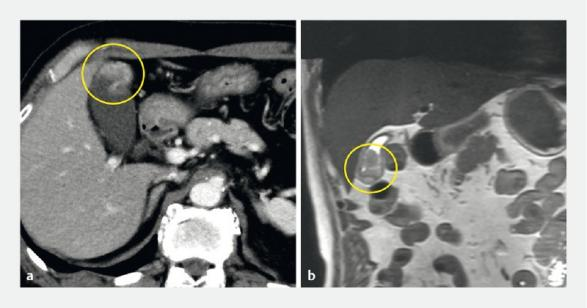

Fig. 1 Abdominal ultrasonography of gallbladder cancer, showing a protruded lesion (yellow arrowheads) at the gallbladder fundus

图1. 胆囊癌的腹部超声图像,显示胆囊底有一个突出病变(黄色箭头)。

A 79-year-old man presented to our hospital with a gallbladder tumor diagnosed using abdominal ultrasonography (AUS). AUS, contrast-enhanced computed tomography, and magnetic resonance imaging showed a protruded lesion at the gallbladder fundus (Fig. 1, Fig. 2). Endoscopic retrograde cholangiography (ERC) was performed, and cholecystography revealed a contrast agent defect at the gallbladder fundus (Fig. 3).

患者,男,79岁,入院后通过腹部超声检查(AUS)诊断出患有胆囊肿瘤。AUS、对比增强计算机断层扫描和磁共振成像显示,胆囊底部有一个突出病变(图1、图2)。进行了经内镜逆行性胆管造影(ERC),且胆囊造影显示,胆囊底部造影剂充盈缺损(图3)。